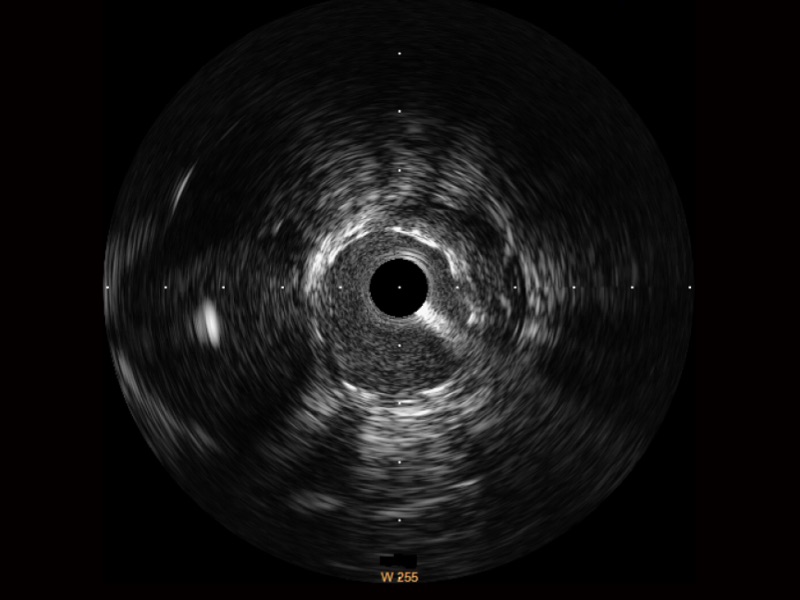

milan米兰宽频IVUS图像

对比传统IVUS导管成像,milan米兰宽频IVUS图像的近场支架梁显影更细腻,远场中膜外血管仍清晰可辨,兼顾远中近,兼顾分辨力与穿透深度